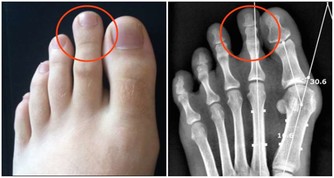

有趣的是,

關於胰臟脂肪多到什麼程度才會危害健康,

每個人的情況都不一樣。

這也就是為什麼,

有些人身材苗條也患有糖尿病,

有的人體重過重卻沒有罹病。